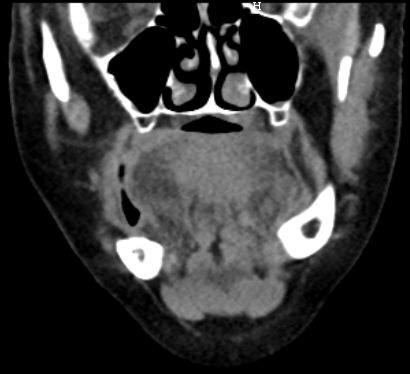

63-jähriger Mann mit Leberzirrhose und ACI-Stenose.

Es besteht ein Hypopharynx - Karzinom und ein Weichgaumenkarzinom mit Übergang auf den harten Gaumen.![]() | |||||||||||||||||